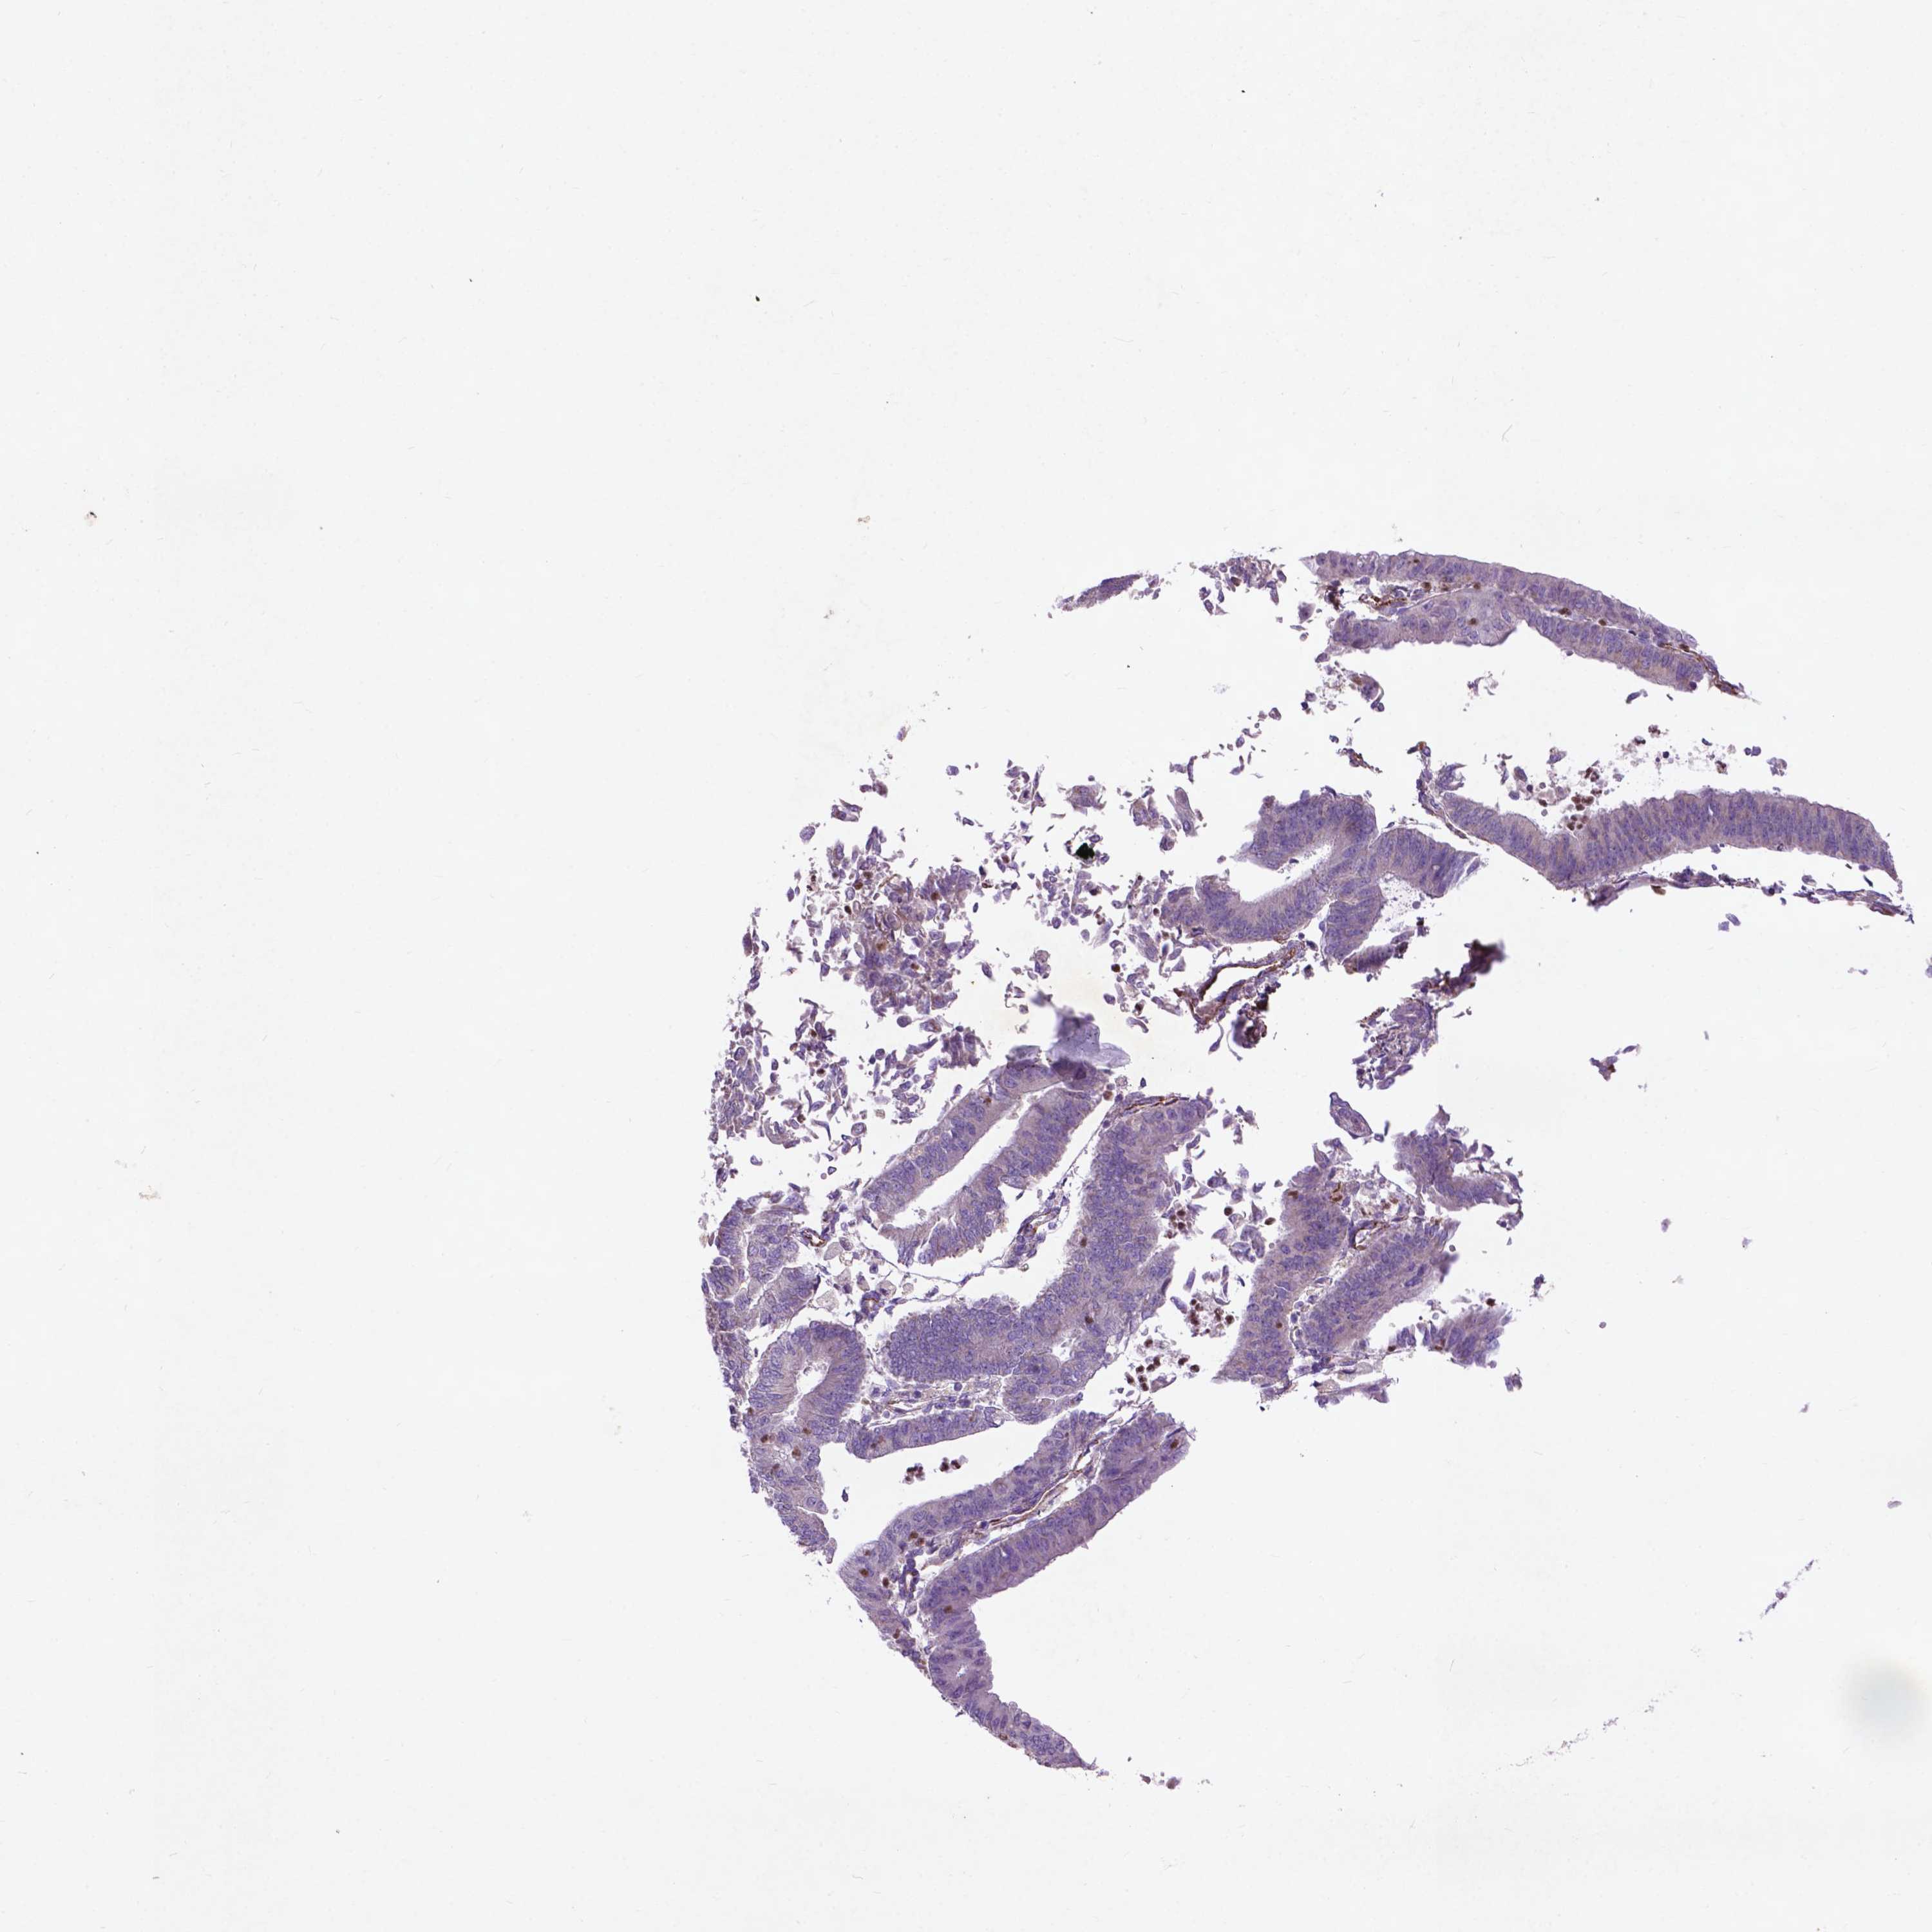

ENDOMETRIAL CANCER - Protein expressioni

A mouse-over function shows sample information and annotation data. Click on an image to view it in a full screen mode. Samples can be filtered based on level of antibody staining by selecting one or several of the following categories: high, medium, low and not detected. The assay and annotation is described here.

Note that samples used for immunohistochemistry by the Human Protein Atlas do not correspond to samples in the TCGA dataset.

Antibody stainingi

Antibody staining in the annotated cell types in the current human tissue is reported as not detected, low, medium, or high, based on conventional immunohistochemistry profiling in selected tissues. This score is based on the combination of the staining intensity and fraction of stained cells.

Each image is clickable and will lead to virtual microscopy that enables deeper exploration of all samples and also displays staining intensity scores, fraction scores and subcellular localization as well as patient and tissue information for each sample.

Antibody HPA068093

Adenocarcinoma, NOS

Adenocarcinoma, metastatic, NOS